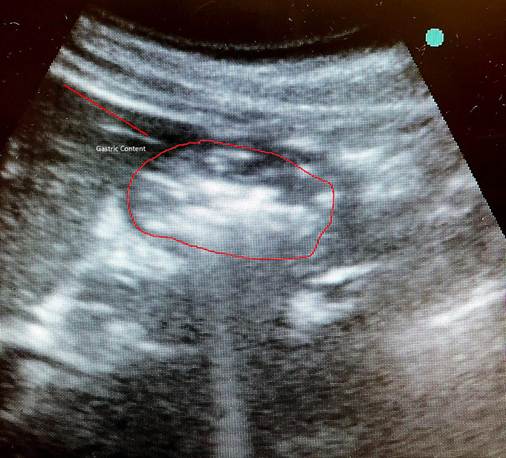

The treating anesthesiologists performed the gastric US in the supine and right lateral decubitus positions. The result showed a full stomach with images suggestive of solid and liquid food content (Figure 1).

The patient received 10 mg of metoclopramide and 40 mg of omeprazole, and the decision was made to repeat the gastric US two hours after this premedication (14 hours of fasting); the result showed a decrease in liquid content but solid contents still present (Figure 2). The surgical procedure was deferred due to high risk of bronchoaspiration and rescheduled after three half-lives of semaglutide.